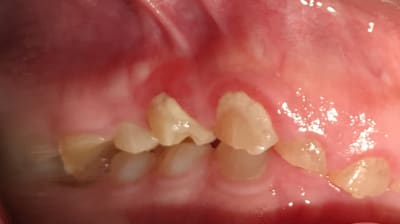

Bonjour je suis lenovo ici . Quelqu’un pourrait-il me donner toutes les étapes pour faire ce cas ? Que faut-il faire précisément ? Le patient n’a pas de contraintes financières. Pas de lésions apicales. Uniquement des usures de dents.

Les photos ne sont pas dingues, mais les usures semblent très majoritairement antérieures. Pourquoi?

Et le fait que 17 18 27 28 semblent intactes alors qu'apparemment il y a des antagonistes intactes aussi

Je suspecte un cas d'ortho non traité sous jacent XXL ... que j'aimerais voir sa télé de profil ...